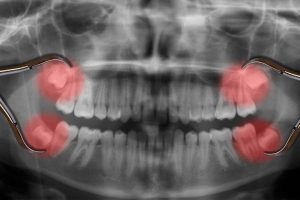

[caption id="attachment_7504" align="alignleft" width="380"]

20 lik diş röntgeni[/caption]